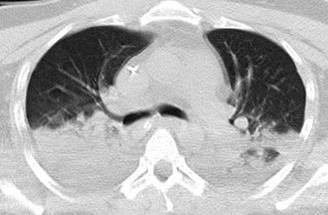

Durante su estancia en la UCI se inicia protocolo de estudio ante deterioro neurológico súbito y fiebre, se realiza punción lumbar con líquido cefalorraquídeo normal, tomografía de cráneo simple a su ingreso y a las 72 horas en las cuales se descarta evento cerebrovascular. PAR y PCR COVID negativos, cultivo de secreción bronquial, urocultivo, hemocultivo central y periférico negativos. La tomografía de tórax (Figura 1) muestra neumonía lobar bilateral, por lo que se inicia manejo antimicrobiano para patógenos atípicos ante paciente inmunosuprimido. Panel de neumonía por método RT-PCR FilmArray de secreción bronquial negativo, así como PCR GeneXpert para Mycobacterium tuberculosis negativo. Anticuerpos anti-Coccidioides immitis IgG e IgM positivos, concordante con cuadro clínico.